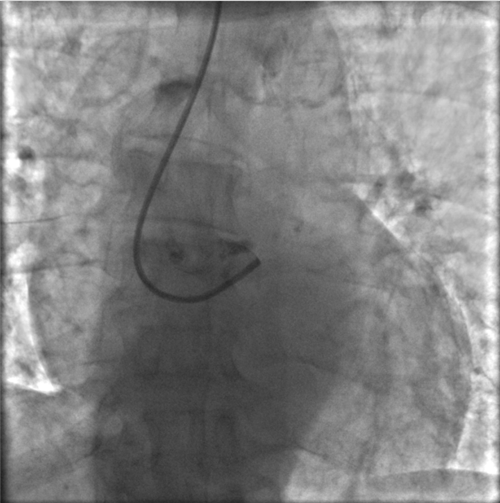

左主干完全閉塞

小心操作導(dǎo)絲及導(dǎo)管,艱難到達(dá)主動(dòng)脈根部,但導(dǎo)管難以“到位”左冠口,“冒煙”見(jiàn)左主干居然完全閉塞了。